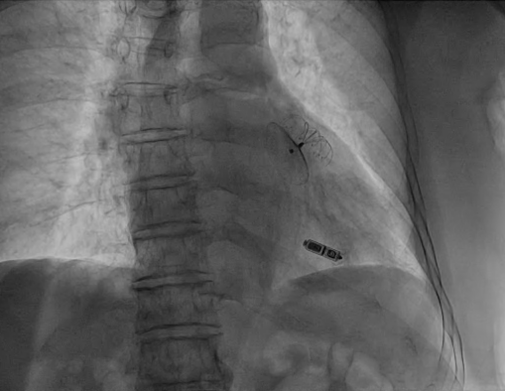

左心耳封堵器及无导线起搏器最终影像